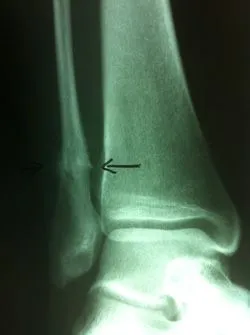

Stress fractures are often a clinical diagnosis as x-rays may be negative initially. The patient would typically experience pain and swelling across the top of the metatarsals. The pain would be mild in the morning. However, would get worse with weight-bearing. When x-rays are negative these problems are still treated as a fracture. X-rays taken 14-21 days after the injury will often show healing of the stress fracture by bone callus along the shaft of the bone.

Stress fractures that occur towards the end of the bone in the metaphyseal region often go nondisplaced after the healing process.

Stress fractures that occur in the midportion of the metatarsal can displace up, causing the potential for future problems in the metatarsal head region.